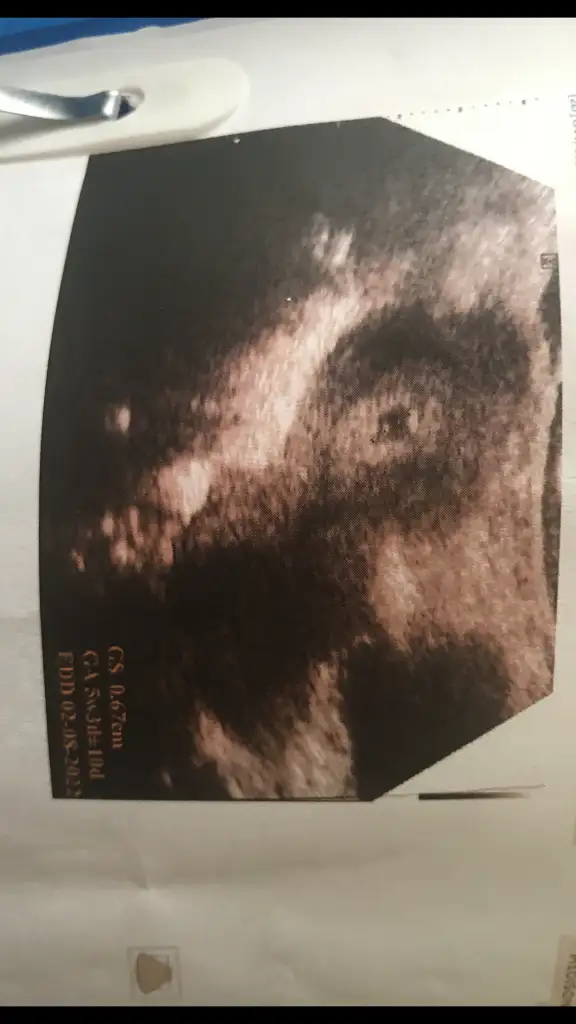

Kızlar bu arada akşam üstü kanamam geldi böyle normal bildiğimiz kırmızı kan yani doktorumla sürekli iletişim halindeyim bazen çift embriyodan biri tutunmayınca böyle şeyler olabiliyor birde bu bebekler biraz nazlı oluyor malum tüp bebek dedi yatıyorum şimdi bol bol WC harici kalkmıyorum arada silince pembe geliyor okadar inşallah oda geçer